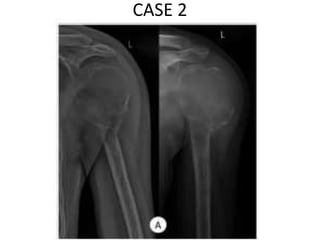

CASE 2

• 42.

• 43.

• 44.

• 45.

• 46.

• 47.